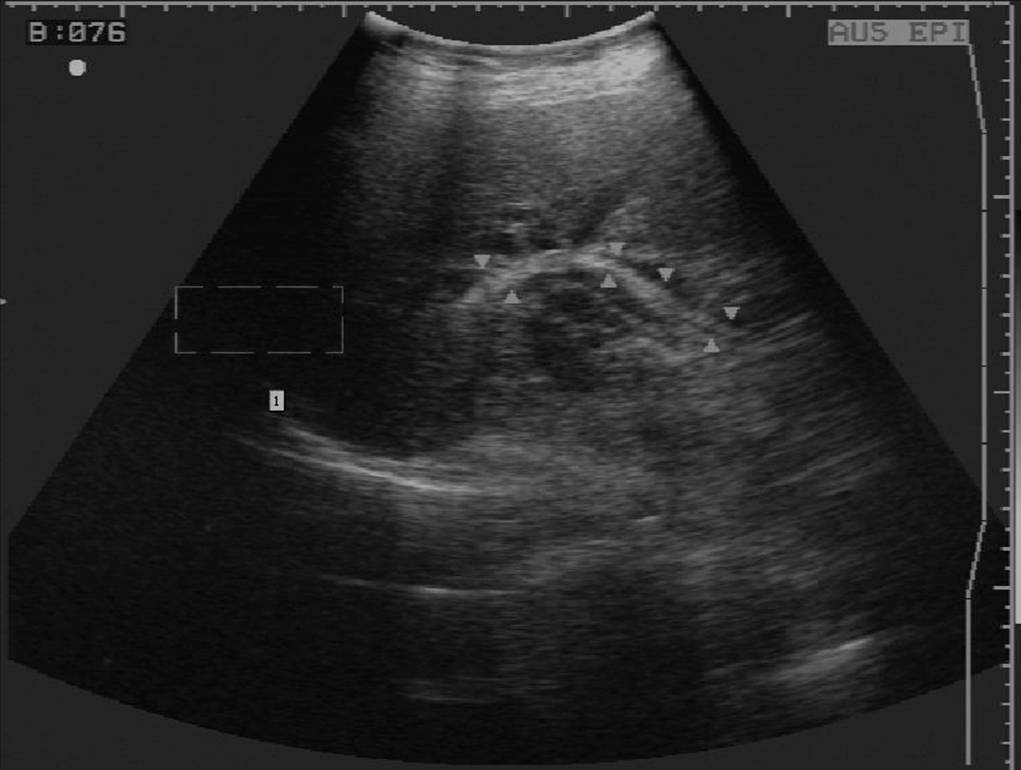

4 胆道蛔虫病